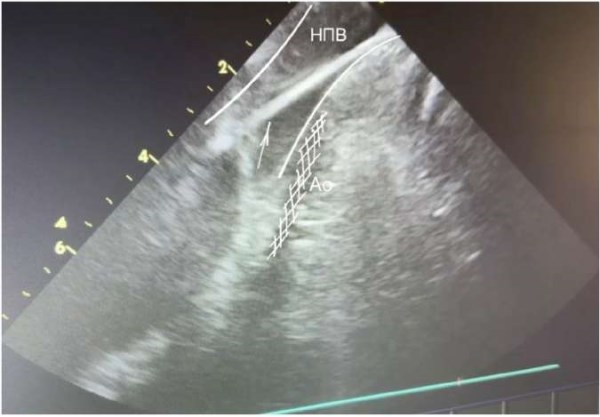

Основными УЗ анатомическими ориентирами при проведении УЗ катетера являются подвздошные артерии, брюшная аорта, печень. Для выведения данного изображения необходимо плавно провести датчик эхокардиографии по подвздошной вене, развернув основную метку (нижнюю неподвижную) в области 3 часов. Если возникают трудности в прохождении датчика в нижней полой вене (НПВ) — верхнюю метку датчика (A/P) нужно плавно повернуть в сторону метки «A». По УЗ исследованию: датчик нырнет в просвет НПВ, плавно продвигаем датчик далее в просвет на 1-2 см, после — поворачиваем метку «А» в исходное положение (рис. 1).

Рис. 1. Проводник в НПВ (белая стрелка). Видимый просвет аорты заштрихован в белую сетку.

Сокращения: Ао — брюшной отдел аорты, НПВ — нижняя полая вена.